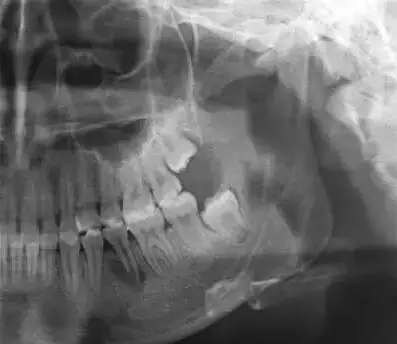

5、X線檢查可見髓室頂中心有向咬合面中央部突起的畸形部分,并常見未發(fā)育完成呈喇叭形的根尖部。